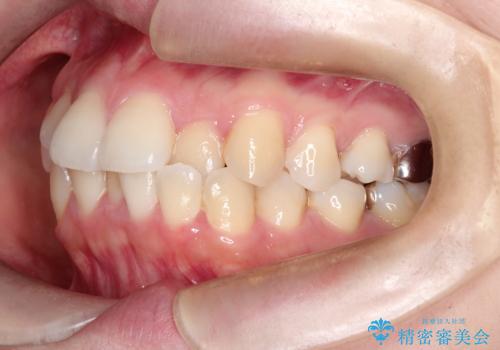

【ワイヤー矯正】口元を下げたい、下の歯の凹凸を無くしたい

- 主訴:口元を下げて前突感を無くしたい、下の歯の凹凸も無くしたい

右側第二小臼歯、左側第一小臼歯、下顎両側第一小臼歯を抜歯しワイヤ-矯正を行いました。

骨格的顎の変位を認めたため、顔貌に対しピッタリ上下の歯の正中を合わせることは難しいと説明し、上下左右計4本小臼歯を抜歯しワイヤー矯正治療を行いました。